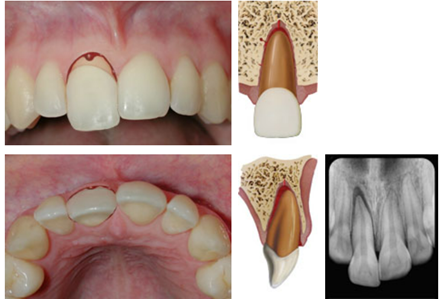

dx lateral luxation

A

Displaced usually in palatal/lingual or labial direction

High metallic/ankylotic sound

Usually mobile

Sensibility tests will likely give a lack of response except for teeth with minor displacements.

* The test is important in assessing risk of healing complications. A positive result at the initial examination indicates a reduced risk of future pulp necrosis.

Occlusal, PA and 2 eccentric exposures from diff horizontal angulations

* Widened PA ligament space